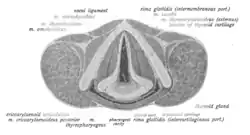

| Healthy vocal folds. Contact granulomas may form in the posterior part of the larynx. | |